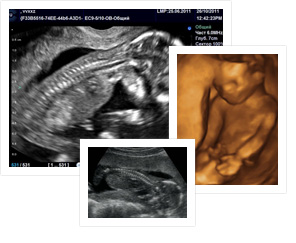

На 28 неделе беременности глаза ребенка широко открыты, он реагирует на яркий свет, просвечивающий сквозь живот. У малыша начинается решающая стадия в развитии коры головного мозга. Шестимесячный плод реагирует на раздражители почти так же, как доношенный ребенок. У него растут волосы, вся голова может быть покрыта ими. Кожа у него остается сморщенной. К этому времени ваш малыш накопил достаточно жировой ткани и ему не страшны преждевременные роды. На УЗИ видно, как поднимается и опускается грудная клетка. Такие дыхательные упражнения не только укрепляют мускулы, но и способствуют нормальному развитию легких. Если бы малыш не вдыхал околоплодную жидкость, легкие остались бы маленькими и после рождения не обеспечили бы нужное количество кислорода.

Длина от темени до крестца — около 27 см. Вес — примерно 1400 г.